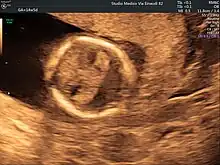

- Ultrasound (prenatally)